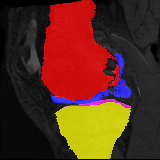

Knee MRI experiment: We test our method on 3D knee MRIs from the Osteoarthritis Initiative (OAI) 111https://nda.nih.gov/oai/ and corresponding segmentations of femur and tibia as well as femoral and tibial cartilage [1]. From a total of 507 labeled images, we use 200 for training, 53 for validation, and 254 for testing. To test registration performance we use 10,000 random image pairs from the test set. All images are affinely registered to an atlas built from the training images, resampled to isotropic spacing of 1mm, cropped to and intensity normalized to [0,1]. In addition, right knee images are flipped to be consistent with left knees. For training, the loss weights are , , and based on approximate hyper-parameter tuning. Note that when computing from the displacements, the image coordinates are scaled to [-1, 1] for each dimension following the convention in the interpolation function of PyTorch.

Results: All trained networks are evaluated using Dice overlap scores between predictions and the manual segmentations for the segmentation network, or between the warped moving segmentations and the target segmentations for the registration network. Tabs. 1 and 2 show results for the knee and brain MRI experiments respectively in Dice scores (%). Fig. 2 shows examples of knee MRI registrations and brain MRI segmentations.

Knee results: On knee MRIs, our method improves segmentation scores over separately learned networks by about 1.2 and 0.5, and registration scores increase by about 3.1 and 3.0, when training with 5 and 10 manual segmentation respectively. Especially for the challenging cartilage structures, our joint learning boosts segmentation by 1.4 and 0.7, and registration by 5.5 and 5.2 for N=5 and N=10 respectively.

Qualitative results: DA achieves more anatomically consistent registrations than the mono-networks on the knee (Fig. 2) and Brain MRI samples (see supplementary material).